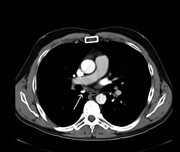

Superior vena cava repair with left brachiocephalic vein flap

Hiroyoshi Tsubochi and others

Journal of Surgical Case Reports, Volume 2016, Issue 3, March 2016, rjw015, https://doi.org/10.1093/jscr/rjw015